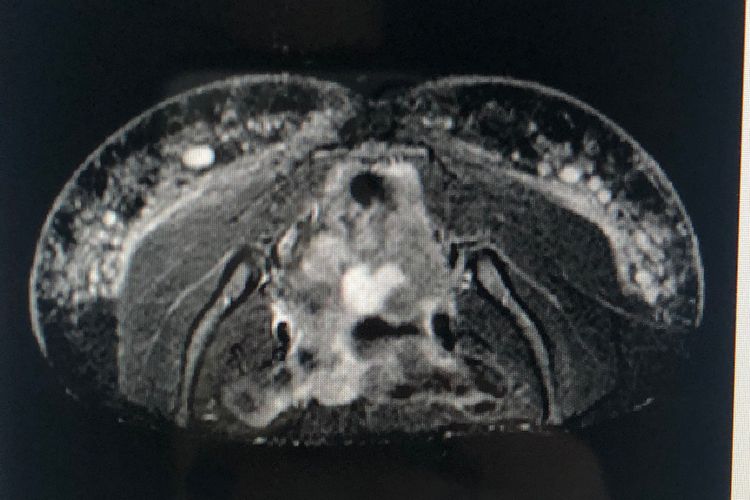

WebLos biopolímeros son macromoléculas de diferentes orígenes, derivados del petróleo, de origen vegetal y muchos son de origen sintético. En este último caso, la mayoría son. WebAplicar biopolímeros en los glúteos puede ser algo muy riesgoso para la salud, por ello aquí te mostramos algunos síntomas que nos indican que se debe extraer. WebSe trata de un procedimiento quirúrgico en el que se aplican diversas técnicas que permiten retirar parcialmente el material inyectado en los glúteos. En la actualidad es posible.